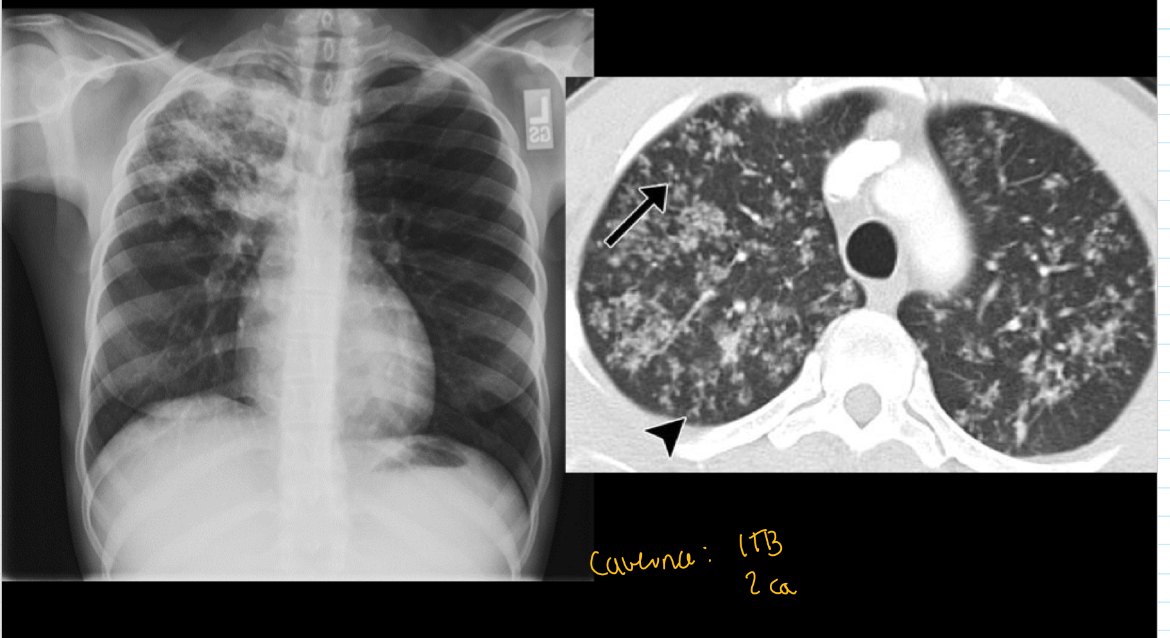

Q

SI VES cavernas en q piensas

A

1: tb

2: cancer

Que patrón de tb es

q es y como sabes

Tb x las cavernas de aire